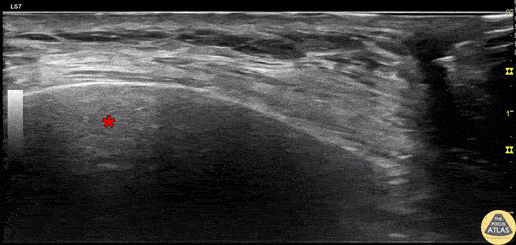

60s F presented to the ED three days after a fall at home, complaining of right chest pain, and was found to have multiple rib fractures on CT with a small amount of hemothorax and blood in the horizontal fissure. A serratus anterior plane block was performed using an in-plane approach to inject anesthetic in the fascial plane between the pectoralis minor and serratus anterior muscles (not shown), followed by this injection into the fascial space between the rib and serratus anterior. Additionally, fluid (likely blood) can be seen here in the pleural space below the rib. 30 minutes after the nerve block, the patient was feeling much improved, her performance on incentive spirometry improved markedly, and she requested discharge. Dr. Michael Heffler, PGY3 Denver Health Residency in Emergency Medicine